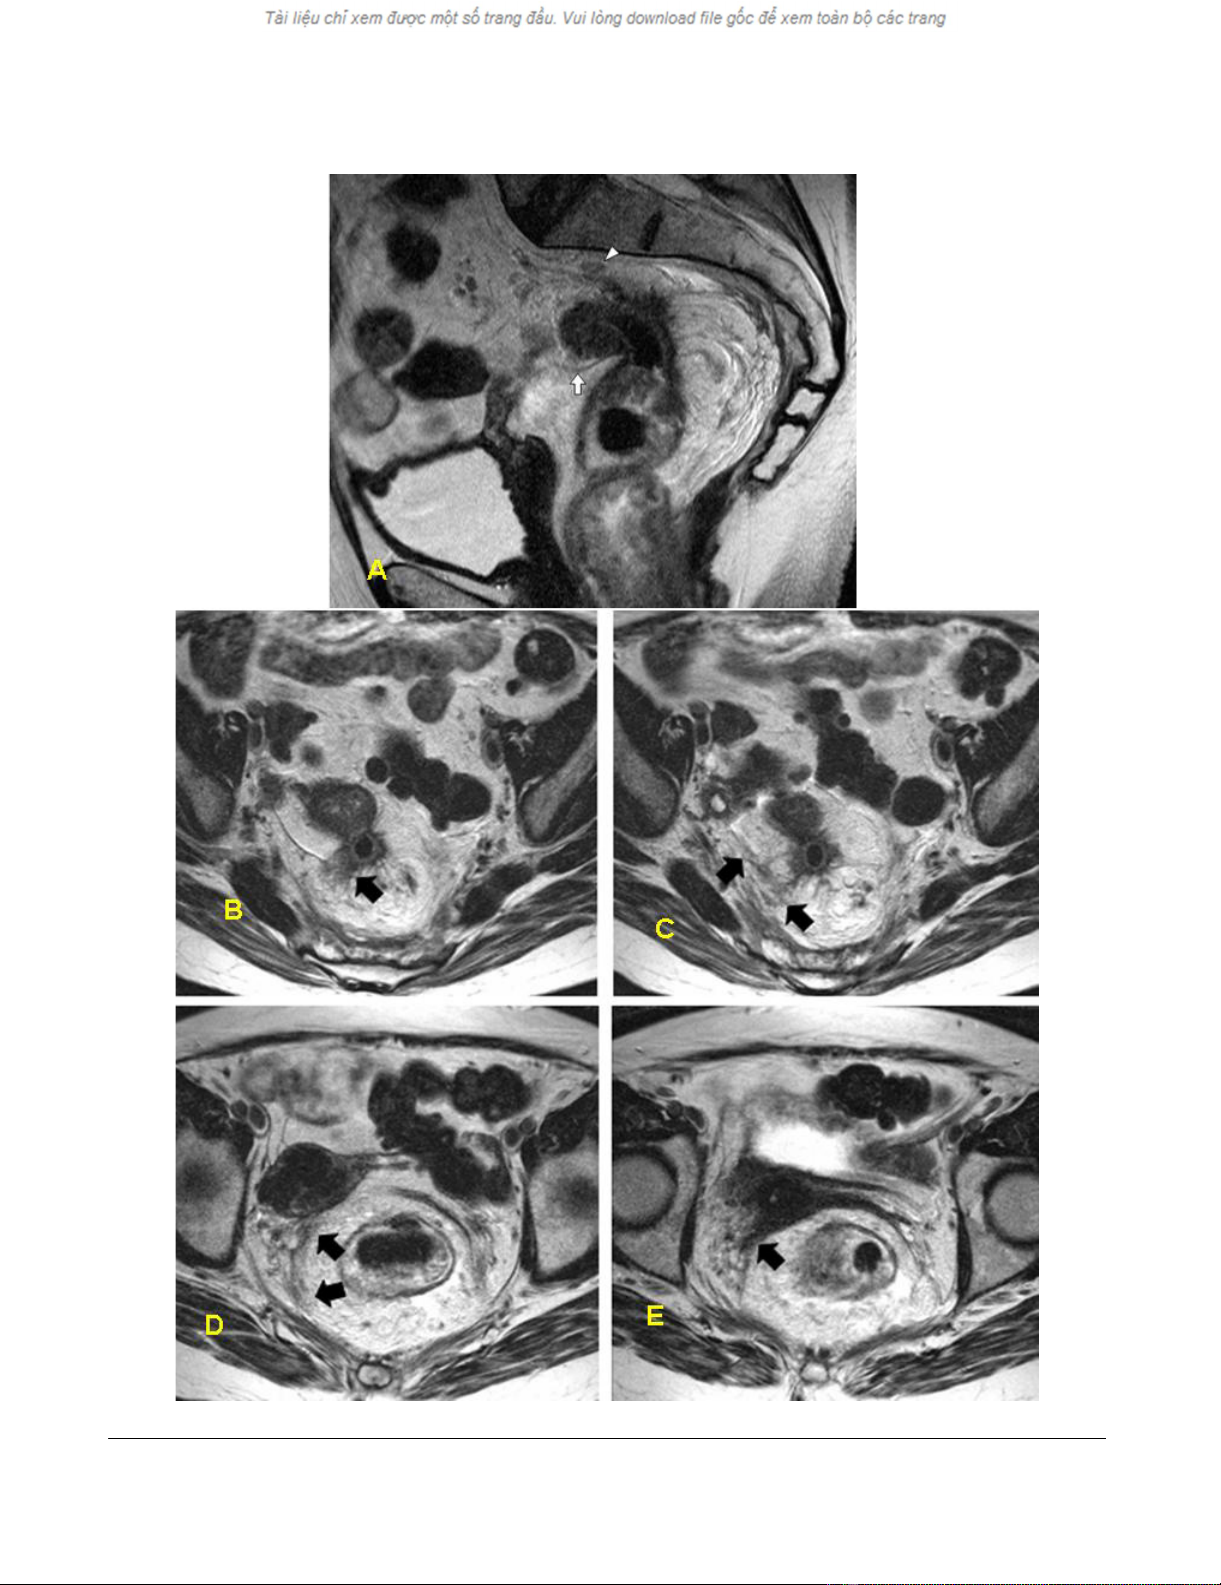

false negative case and 16 true negatives (table 2). Figure

1 demonstrates the false-negative case. In this case, there

appears to be no continuity between the tumor and the

uterus. However, histopathological examination showed

tumor invasion along the fascia, reaching the posterior

wall of the uterus and the left adnexa. The radiologist

failed to ascertain the anterior extension of the tumor cor-

rectly.